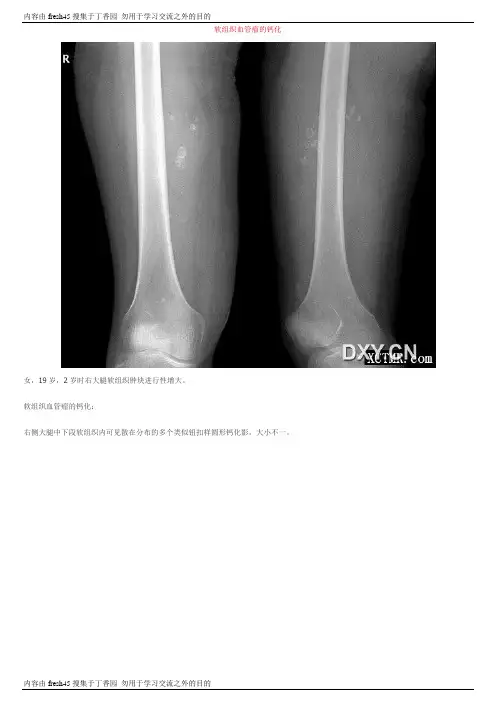

软组织血管瘤的钙化女,19岁,2岁时右大腿软组织肿块进行性增大。

软组织血管瘤的钙化:右侧大腿中下段软组织内可见散在分布的多个类似钮扣样圆形钙化影,大小不一。